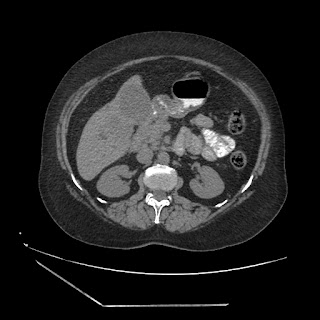

A 70 years old woman with Obstractive jaundice & palpable GB